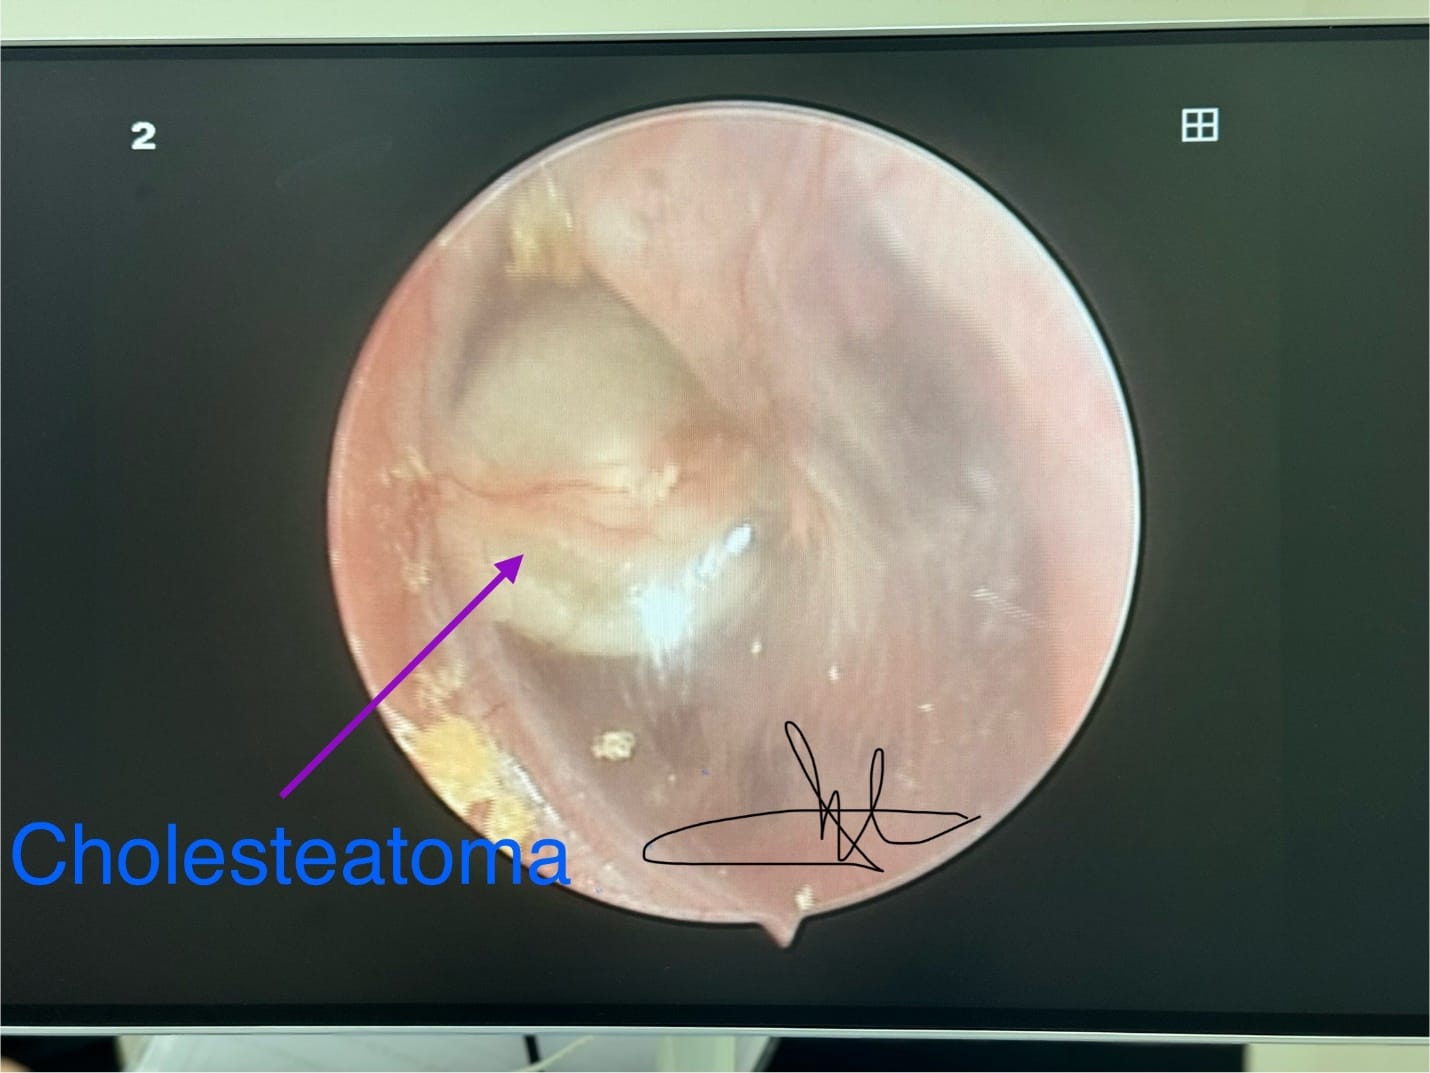

Hình ảnh nội soi tai khối Cholesteatoma.

- Hình ảnh nội soi tai thấy khối màu trắng phía sau màng tai bình thường.

- Phần lớn các trường hợp Cholesteatoma bẩm sinh tai giữa quan sát thấy ở góc ¼ trước trên. Tuy nhiên, các vị trí như góc sau màng nhĩ, hoặc chiếm toàn bộ màng nhĩ đều có thể gặp.